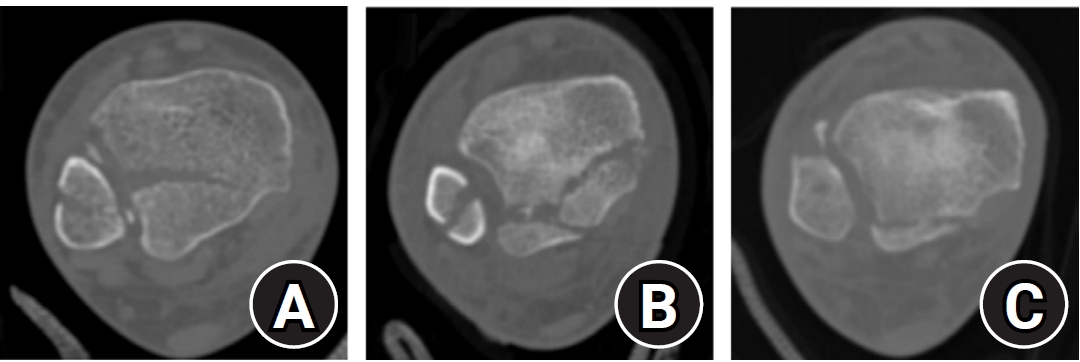

Fig. 2.

Haraguchi classification of posterior malleolar fractures. (A) Type I: posterolateral-oblique type. (B) Type II: medial-extension type. (C) Type III: small-shell type.

Regarding posterior malleolar fracture morphology, Haraguchi type III (small shell fragment) was more common in the <4.5 cm group, while type II (medial extension) predominated in the ≥4.5 cm group (P<0.001) (Table 2, Fig. 5). Similarly, the Bartonicek classification showed that type 1 (extra-incisural fragment with intact fibular notch) and type 2 (small posterolateral fragment extending into the fibular notch) were more frequent in the <4.5 cm group, whereas type 3 (posteromedial two-part fragment involving the medial malleolus) and type 4 (large posterolateral triangular fragment involving more than one-third of the notch) were predominant in the ≥4.5 cm group (P<0.001).